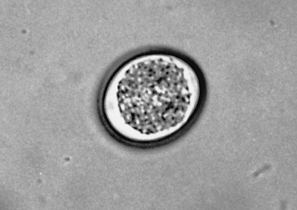

Toxoplasma gondii is another intestinal coccidian of cats. Its oocysts usually are diagnosed using a standard fecal flotation. Oocysts of T. gondii are unsporulated in fresh feces and measure 10 μm by 12 μm. Several immunodiagnostic tests using whole blood or serum are available for diagnosis of T. gondii infection. The prepatent period is highly variable, ranging from 5 to 24 days, and depends on the route of infection.